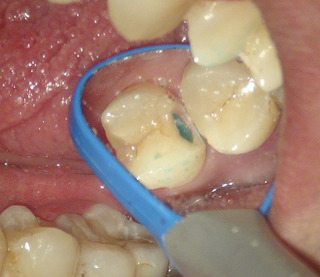

虫歯を染める液で染め出して削る量を最小限に。

水色の部分が虫歯がまだ残っているところ

虫歯を全部とったところ レジンを詰め終わったところ